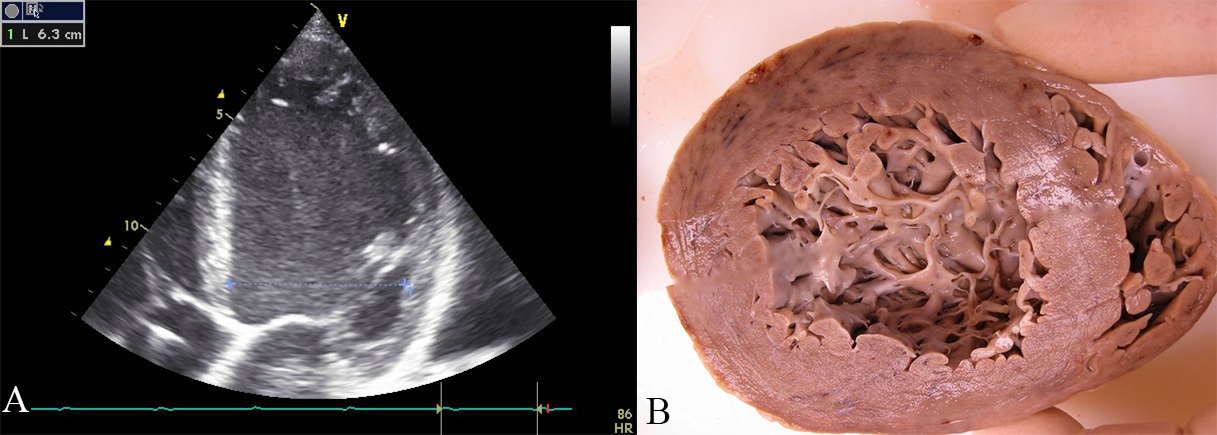

Fig. 1.Echocardiographic and pathoanatomic picture of left ventricular hypertrabeculation/noncompaction. (A) Echocardiographic apical four-chamber-view of a patient with dilated cardiomyopathy. Four trabeculations are visible in the apex of the left ventricle, thus fulfilling the criteria of Stöllberger et al. [10] for left ventricular hypertrabeculation/noncompaction. (B) One week after echocardiography, the patient died due to heart failure. The formaldehyde-fixed heart is opened along the short axis. A heavily trabeculated apical portion of the left ventricle is visible.

Transthoracic echocardiography is the most frequently applied method for diagnosing LVHT because it is non-invasive, without radiation, needs usually no contrast medium, widely available and unexpensive. Echocardiography, on the other side, has disadvantages because it is highly dependent on the experience of the investigator. The image quality may be impeded, especially in the apical region, where LVHT is frequently located (Fig. 1B). Thus, by echocardiography, LVHT may be over- as well as under-diagnosed [4]. Currently, different echocardiographic criteria are used and their application may influence the prevalence of LVHT (Table 1, Ref. [2, 11, 12]). A further problem in diagnosing LVHT by echocardiography is the poor inter- and intra-observer agreement, especially when investigators from different laboratories are compared [13].